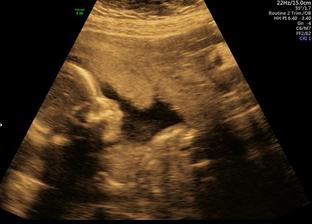

12.6.2017 Screening v 1 trimestru. JSI KRÁSNÁ ZDRAVÁ HOLČIČKA!!! TP podle MS i UZ 18.12.2017